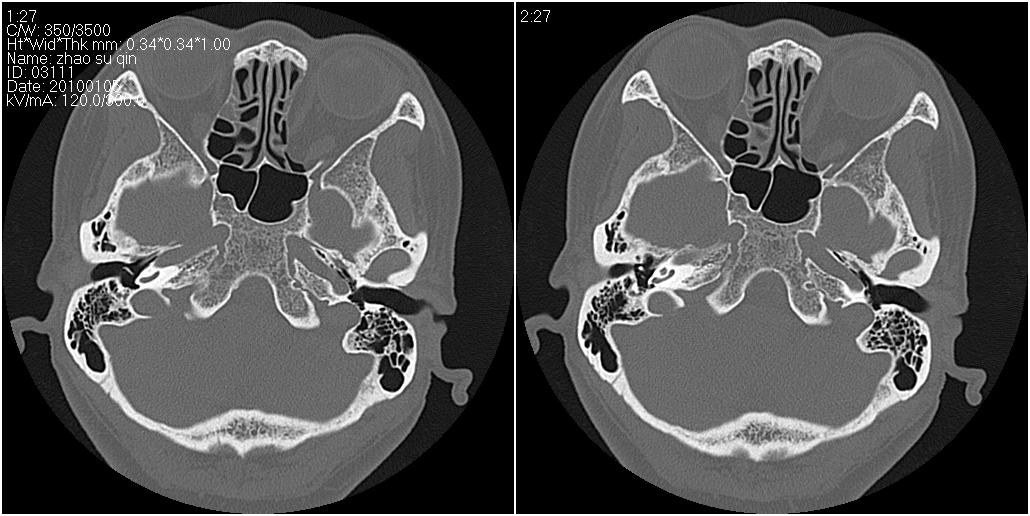

标题: CT24015:一个头部外伤患者进行鉴定,除了左侧筛板骨折,哪 [打印本页]

标题: CT24015:一个头部外伤患者进行鉴定,除了左侧筛板骨折,哪

左眶下裂部好像有骨折 似有小碎骨片

1)左侧筛板骨折。2)双侧筛窦炎症(或积血)。